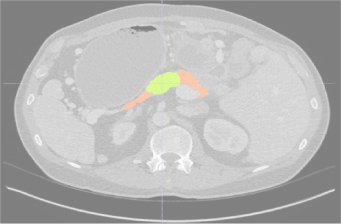

Creating large-scale and well-annotated datasets to train AI algorithms is crucial for automated tumor detection and localization. However, with limited resources, it is challenging to determine the best type of annotations when annotating massive amounts of unlabeled data. To address this issue, we focus on polyps in colonoscopy videos and pancreatic tumors in abdominal CT scans; both applications require significant effort and time for pixel-wise annotation due to the high dimensional nature of the data, involving either temporary or spatial dimensions. In this paper, we develop a new annotation strategy, termed Drag&Drop, which simplifies the annotation process to drag and drop. This annotation strategy is more efficient, particularly for temporal and volumetric imaging, than other types of weak annotations, such as per-pixel, bounding boxes, scribbles, ellipses, and points. Furthermore, to exploit our Drag&Drop annotations, we develop a novel weakly supervised learning method based on the watershed algorithm. Experimental results show that our method achieves better detection and localization performance than alternative weak annotations and, more importantly, achieves similar performance to that trained on detailed per-pixel annotations. Interestingly, we find that, with limited resources, allocating weak annotations from a diverse patient population can foster models more robust to unseen images than allocating per-pixel annotations for a small set of images. In summary, this research proposes an efficient annotation strategy for tumor detection and localization that is less accurate than per-pixel annotations but useful for creating large-scale datasets for screening tumors in various medical modalities.